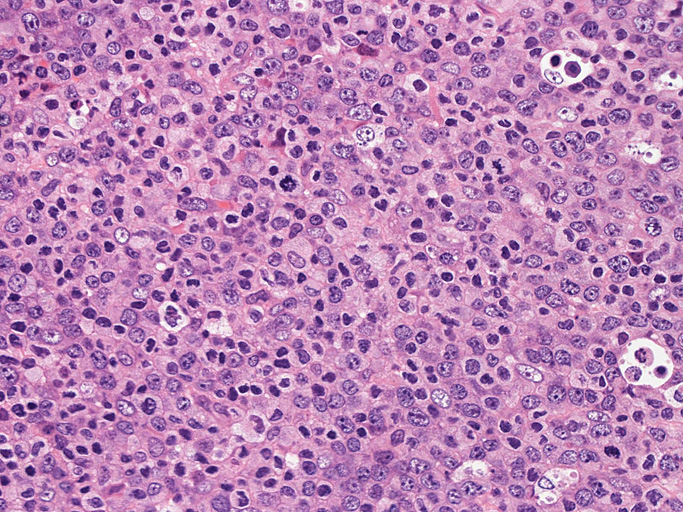

いわゆるanaplastic large cellと呼ぶ多型または腎臓型核をもった大型細胞の増殖はみられない。centroblastに似る円形, 卵円形, わずかに切れ込みをもつ核をもつ大型細胞が索状または地図様に集ぞくし, 背景には淡明な細胞質としわのよったhypercrhomaticな核をもつ細胞がシート状に認められる。二種類の細胞がHEでは認められる。

ALK-positive ALCLのvariant, lymphohistiocytic variantが近いと考える